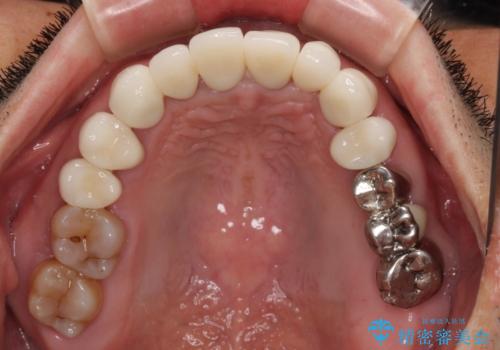

上下ともに前歯のセラミッククラウンによる補綴治療を希望されていましたが、下顎前歯は叢生が強いため、補綴治療前に部分矯正を行って歯列を整えた上で、補綴治療を行うこととしました。

臼歯部には歯周ポケットのある箇所が散見されましたが、まずは前歯を治療したいとのことで、治療を進めました。

ディープバイトにより臼歯部に負担のかかる咬合であったので、補綴治療後には、矯正治療の後戻り防止もかねて、睡眠時にマウスピースを装着するように指示しました。